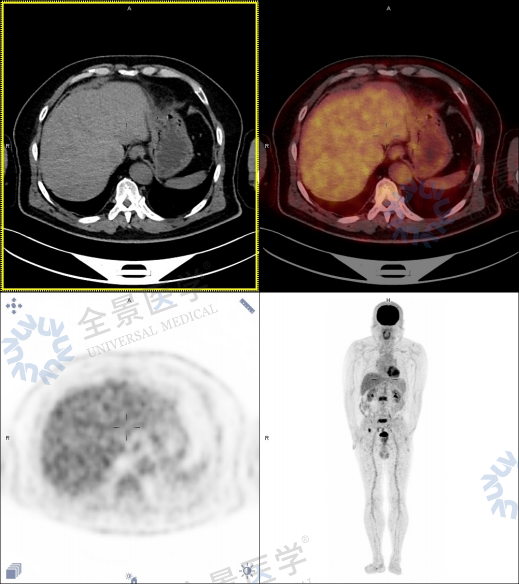

当 PET/CT 的报告逐帧展开时,影像医师的眉头渐渐紧锁:

• 前列腺增大伴 FDG 代谢异常增高,左半腺体 SUVmax 达 4.6,与精囊腺、膀胱后壁分界不清

• 双侧盆壁淋巴结肿大,最大短径 0.9 cm,SUVmax3.7

• 左侧第 2 侧肋、腰 2 椎体等 6 处骨骼出现成骨性转移,SUVmax 高达 6.9

• 肝脏数枚低密度结节,虽代谢略低但仍需排除转移

肝内见数枚直径 2.9 cm 以下稍低密度结节,边界欠清,部分 FDG 摄取略低于肝本底

双侧盆壁见多发淋巴结,大者短径约 0.9 cm,FDG 摄取增高,SUVmax = 3.7。